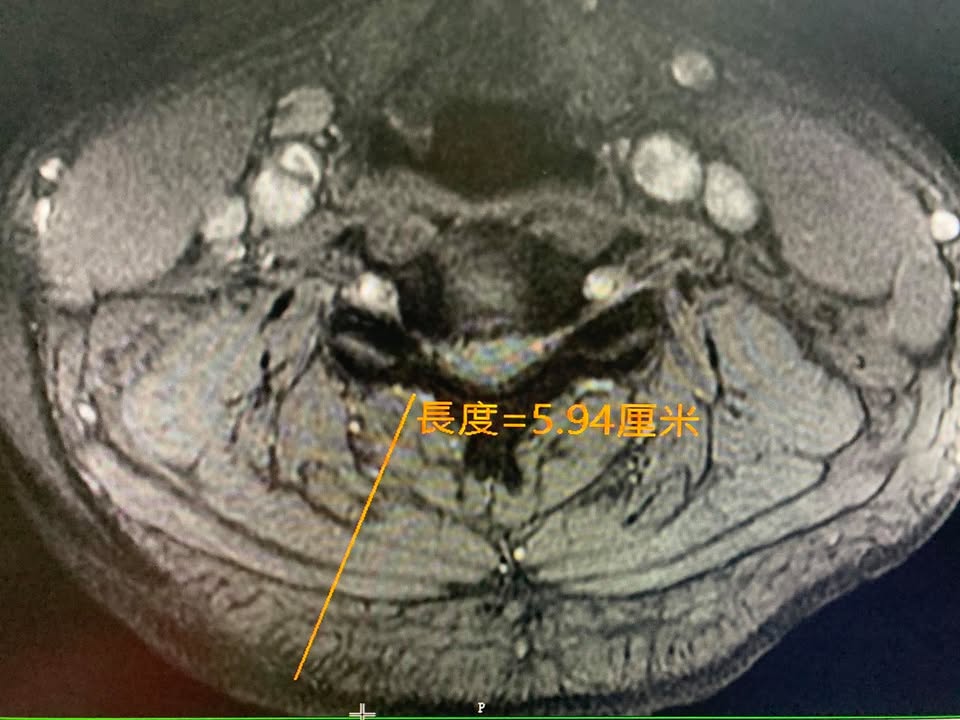

#核磁共振證實C4C5突出壓迫

後來在今年去某醫學中心拍攝頸椎核磁共振證實頸椎第五神經根卡壓,因為傳統復健超過三個月仍然沒重大改善,頸椎酸痛到上臂都非常不舒服,經過友人介紹於今年9月底來接受治療

❇️診斷:C4C5椎間盤突出壓迫神經根與硬膜囊